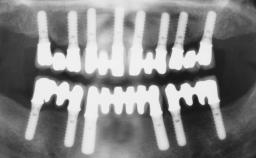

Immediate Loading of Six Implants in the Maxilla and Final Restoration with a Full-Arch CAD/CAM Zirconia FDP

# of Implants 6

Abutment Type CAD/CAM

Prosthesis Type FDP

Loading Protocol Immediate